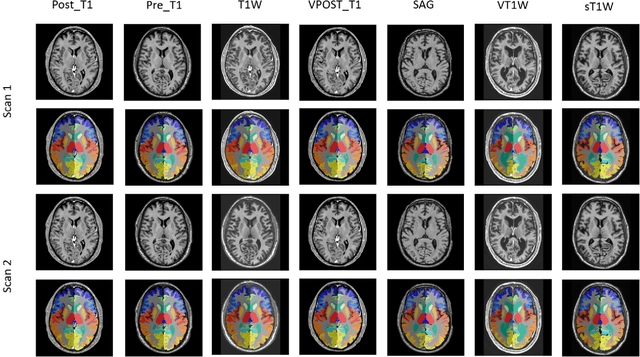

Abstract:Whole brain segmentation on structural magnetic resonance imaging (MRI) is essential for understanding neuroanatomical-functional relationships. Traditionally, multi-atlas segmentation has been regarded as the standard method for whole brain segmentation. In past few years, deep convolutional neural network (DCNN) segmentation methods have demonstrated their advantages in both accuracy and computational efficiency. Recently, we proposed the spatially localized atlas network tiles (SLANT) method, which is able to segment a 3D MRI brain scan into 132 anatomical regions. Commonly, DCNN segmentation methods yield inferior performance under external validations, especially when the testing patterns were not presented in the training cohorts. Recently, we obtained a clinically acquired, multi-sequence MRI brain cohort with 1480 clinically acquired, de-identified brain MRI scans on 395 patients using seven different MRI protocols. Moreover, each subject has at least two scans from different MRI protocols. Herein, we assess the SLANT method's intra- and inter-protocol reproducibility. SLANT achieved less than 0.05 coefficient of variation (CV) for intra-protocol experiments and less than 0.15 CV for inter-protocol experiments. The results show that the SLANT method achieved high intra- and inter- protocol reproducibility.